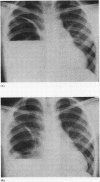

Nine cases of congenital cystic adenomatoid malformation of the lung are described. One was stillborn: two presented in the newborn period (one of them surviving after a lobectomy), and the remaining six were older children all of whom survived after lobectomy. There have been only three cases previously reported in children outside the newborn period. The pathological, clinical, and radiological features are discussed and compared with previously reported cases.